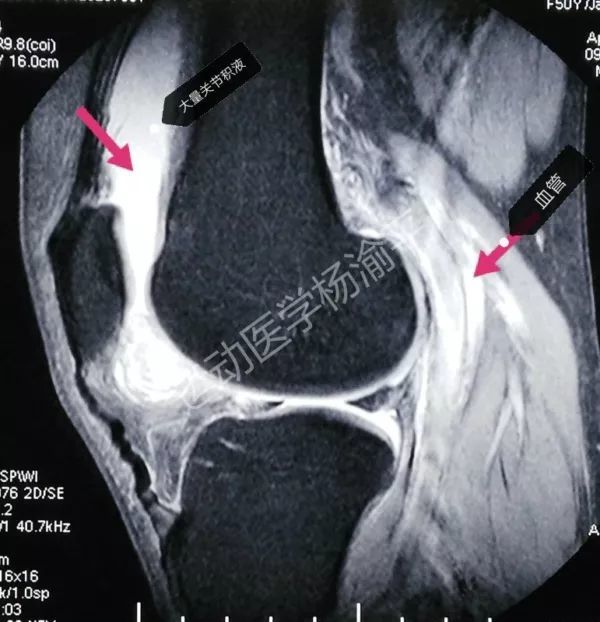

这个病例是膝关节外伤来了拍x光,我看到膝关节腔和髌上滑囊有积液